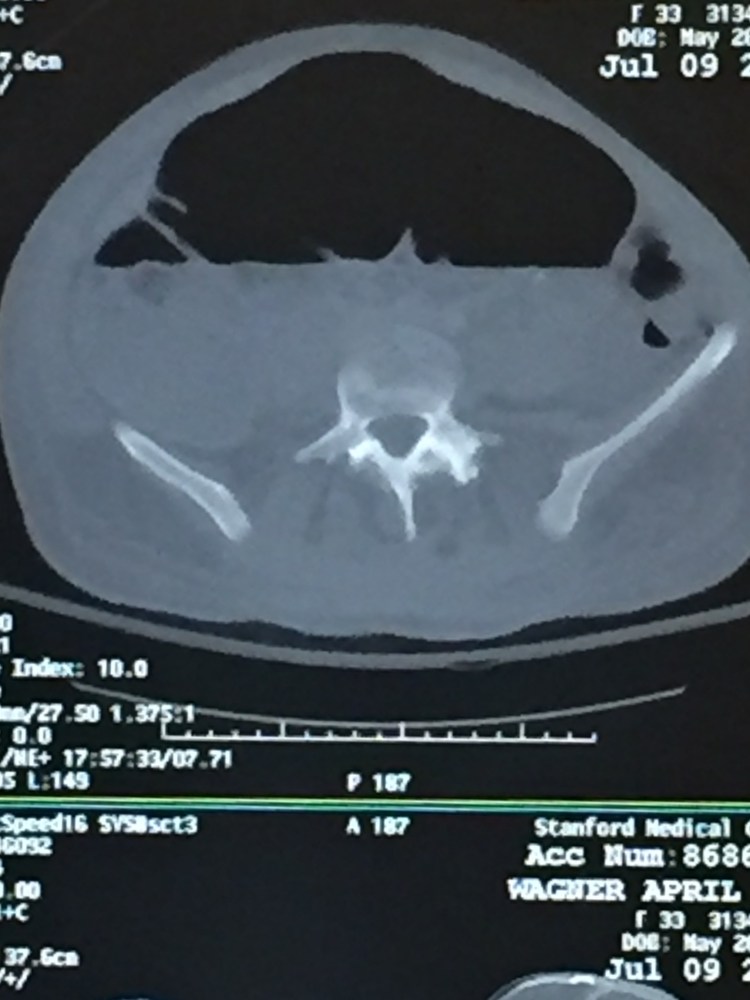

So April has been complaining about abdominal pains for a couple days and she hasn’t been allowed to eat or drink really. Her stomach has been very distended And painful to the touch. Once the MRI was read the Fellow rounded on April and told her the MRI looked great in regards to her spine, but they were concerned about her bowels. He said they were ordering a stat X-ray of her abdomen. The results came back and it looked like she has a large ileus in her bowels, so the doctor wrote orders for her to go to CT stat to get scanned. The CT scan showed she had some very distended bowels, especially her cecum. A colorectal specialist doctor came to see April and told us she has a cecal bascule. A cecal bascule is where the cecum (the beginning of the large intestine) somehow becomes folded over on itself and causes a bowel obstruction. Normally the cecum is about 4cm and April has become distended to 9cm and the only way to fix it is surgery.

CT scan

CT scan – you can see how distended the bowel is.

This is Neil. So with any big surgery the anesthesiologist has to paralyze you. This also means your bowel is paralyzed and stops its normal moving of parastalsis, which is what moves food along to the end of the line. Also, narcotics don’t help and not be able to get up and move doesn’t help. So after surgery it just takes time for your bowels to wake back up and start moving again. In April’s case, somehow her cecum, the start of the large intestines, folded over on itself which caused a blockage. Since there was a blockage, gas, fluids and food just built up there until it became so distended in her abdomen. April honestly looked 3 or 4 months pregnant and the pain was real bad. Normal cecum is 4cm in diameter and hers on the CT measured 9cm, but the doctor told me after surgery it was even bigger than that and quite impressive. The doctor ran her bowel and said everything else looked healthy, but she removed the cecum and about a foot of large intestine.